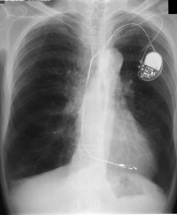

- Age/Sex: 82M

- Chief Complaint: 側傫偲側偔懱偑偩傞偄

- Clinical Course

- 15擭慜 complete AV block偱pacemaker怉偊崬傒

- 嶐擭6寧 COPD偵懳偟偰嵼戭巁慺椕朄

- 嶐擭7寧 寫懹姶弌尰

- 嶐擭8寧 撪壢傊擖堾

- 峛忬態惛嵏偺偨傔I-123峛忬態僔儞僠僌儔僼傿傪梊掕偟偰偄偨偑姵幰偺帠忣偵傛傝戅堾偡傞偙偲偲側偭偨丅

- 戅堾慜偵99mTcO4偵曄峏偟偰峛忬態僔儞僠僌儔僼傿傪巤峴偟偨丅

- Lab. data

- TP:7.8g/dl, T-Bil:1.00mg/dl, ALP:329 IU/L, LAP:66 IU/L,

兞-GTP:114 IU/L, CHE:94IU/L, AST:77.4 IU/L, ALT:40 IU/L,

LDH:140.8 IU/L

- CPK:911IU/L, CPKMB:25.8IU/L

- WBC:3200/兪L, RBC:369枩/兪L, Hb:12.0g/dl, Hct 37.4%, Plt

14.9枩/兪L, CRP 0.1mg/dl

- TSH: 179.76兪U/ml, FT3 0.77pg/ml, FT4 0.66ng/dl,

microsome test 409,600, Anti-TPO Ab >50, Anti-Tg Ab

>100

- Images

- Tc-99m scan: uptake 6.8%

- neck CT